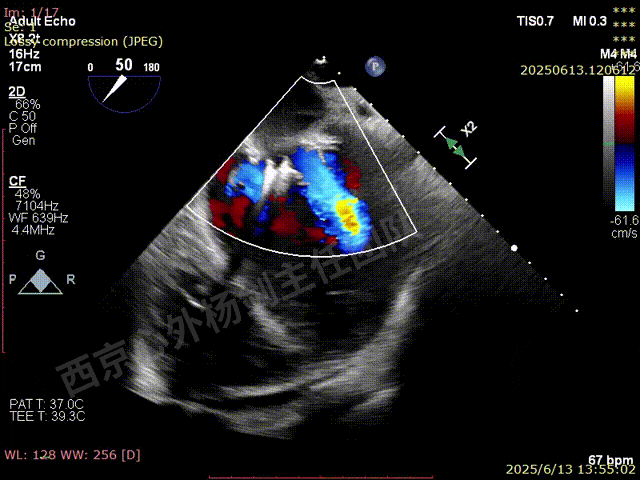

TAVR术后,全心增大,二尖瓣反流重度,三尖瓣反流重度。中量心包积液。左室严重增大,标准图像调整困难。主动脉瓣位带支架人工瓣膜瓣叶启闭正常,主动脉瓣位人工瓣上血流速度Vmax 148cm/s,PGmax 9mmHg,Vmean 86cm/s,PGmean 2mmHg, VTI 34.7cm,瓣周反流(轻)。估测肺动脉收缩压约49mmHg;左室收缩功能明显减低。LVEF:23%,EDV:364ml,ESV:221ml。

彩色血流示:二尖瓣反流缩流颈彩宽6.6mm,面积17cm²,容积30ml;二尖瓣瓣口面积6.6cm²,瓣环内径:左右径34mm,前后径34mm。2区瓣叶长度:前叶36mm,后叶20mm,叶环比1.6. 三尖反流面积17.2cm²,容积33ml,Vmax 291cm/s,PGmax 34mmHg。

TEER术前超声评估

二尖瓣后叶栓系严重,前叶相对错位,反流束沿2区分布广泛,2偏3区处存在反流。

反流宽度至少23mm,因影像调整困难,考虑实际反流更宽。